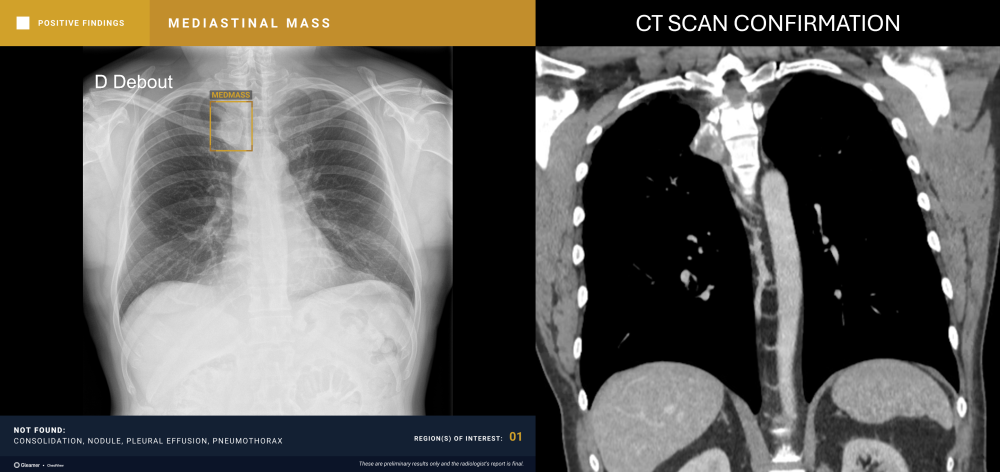

Indication

An 80-year-old male with a previously normal chest X-ray presents for CT evaluation 9 months later, which reveals findings suggestive of lung cancer.

Results

ChestView detected the mediastinal mass on the initial X-ray.